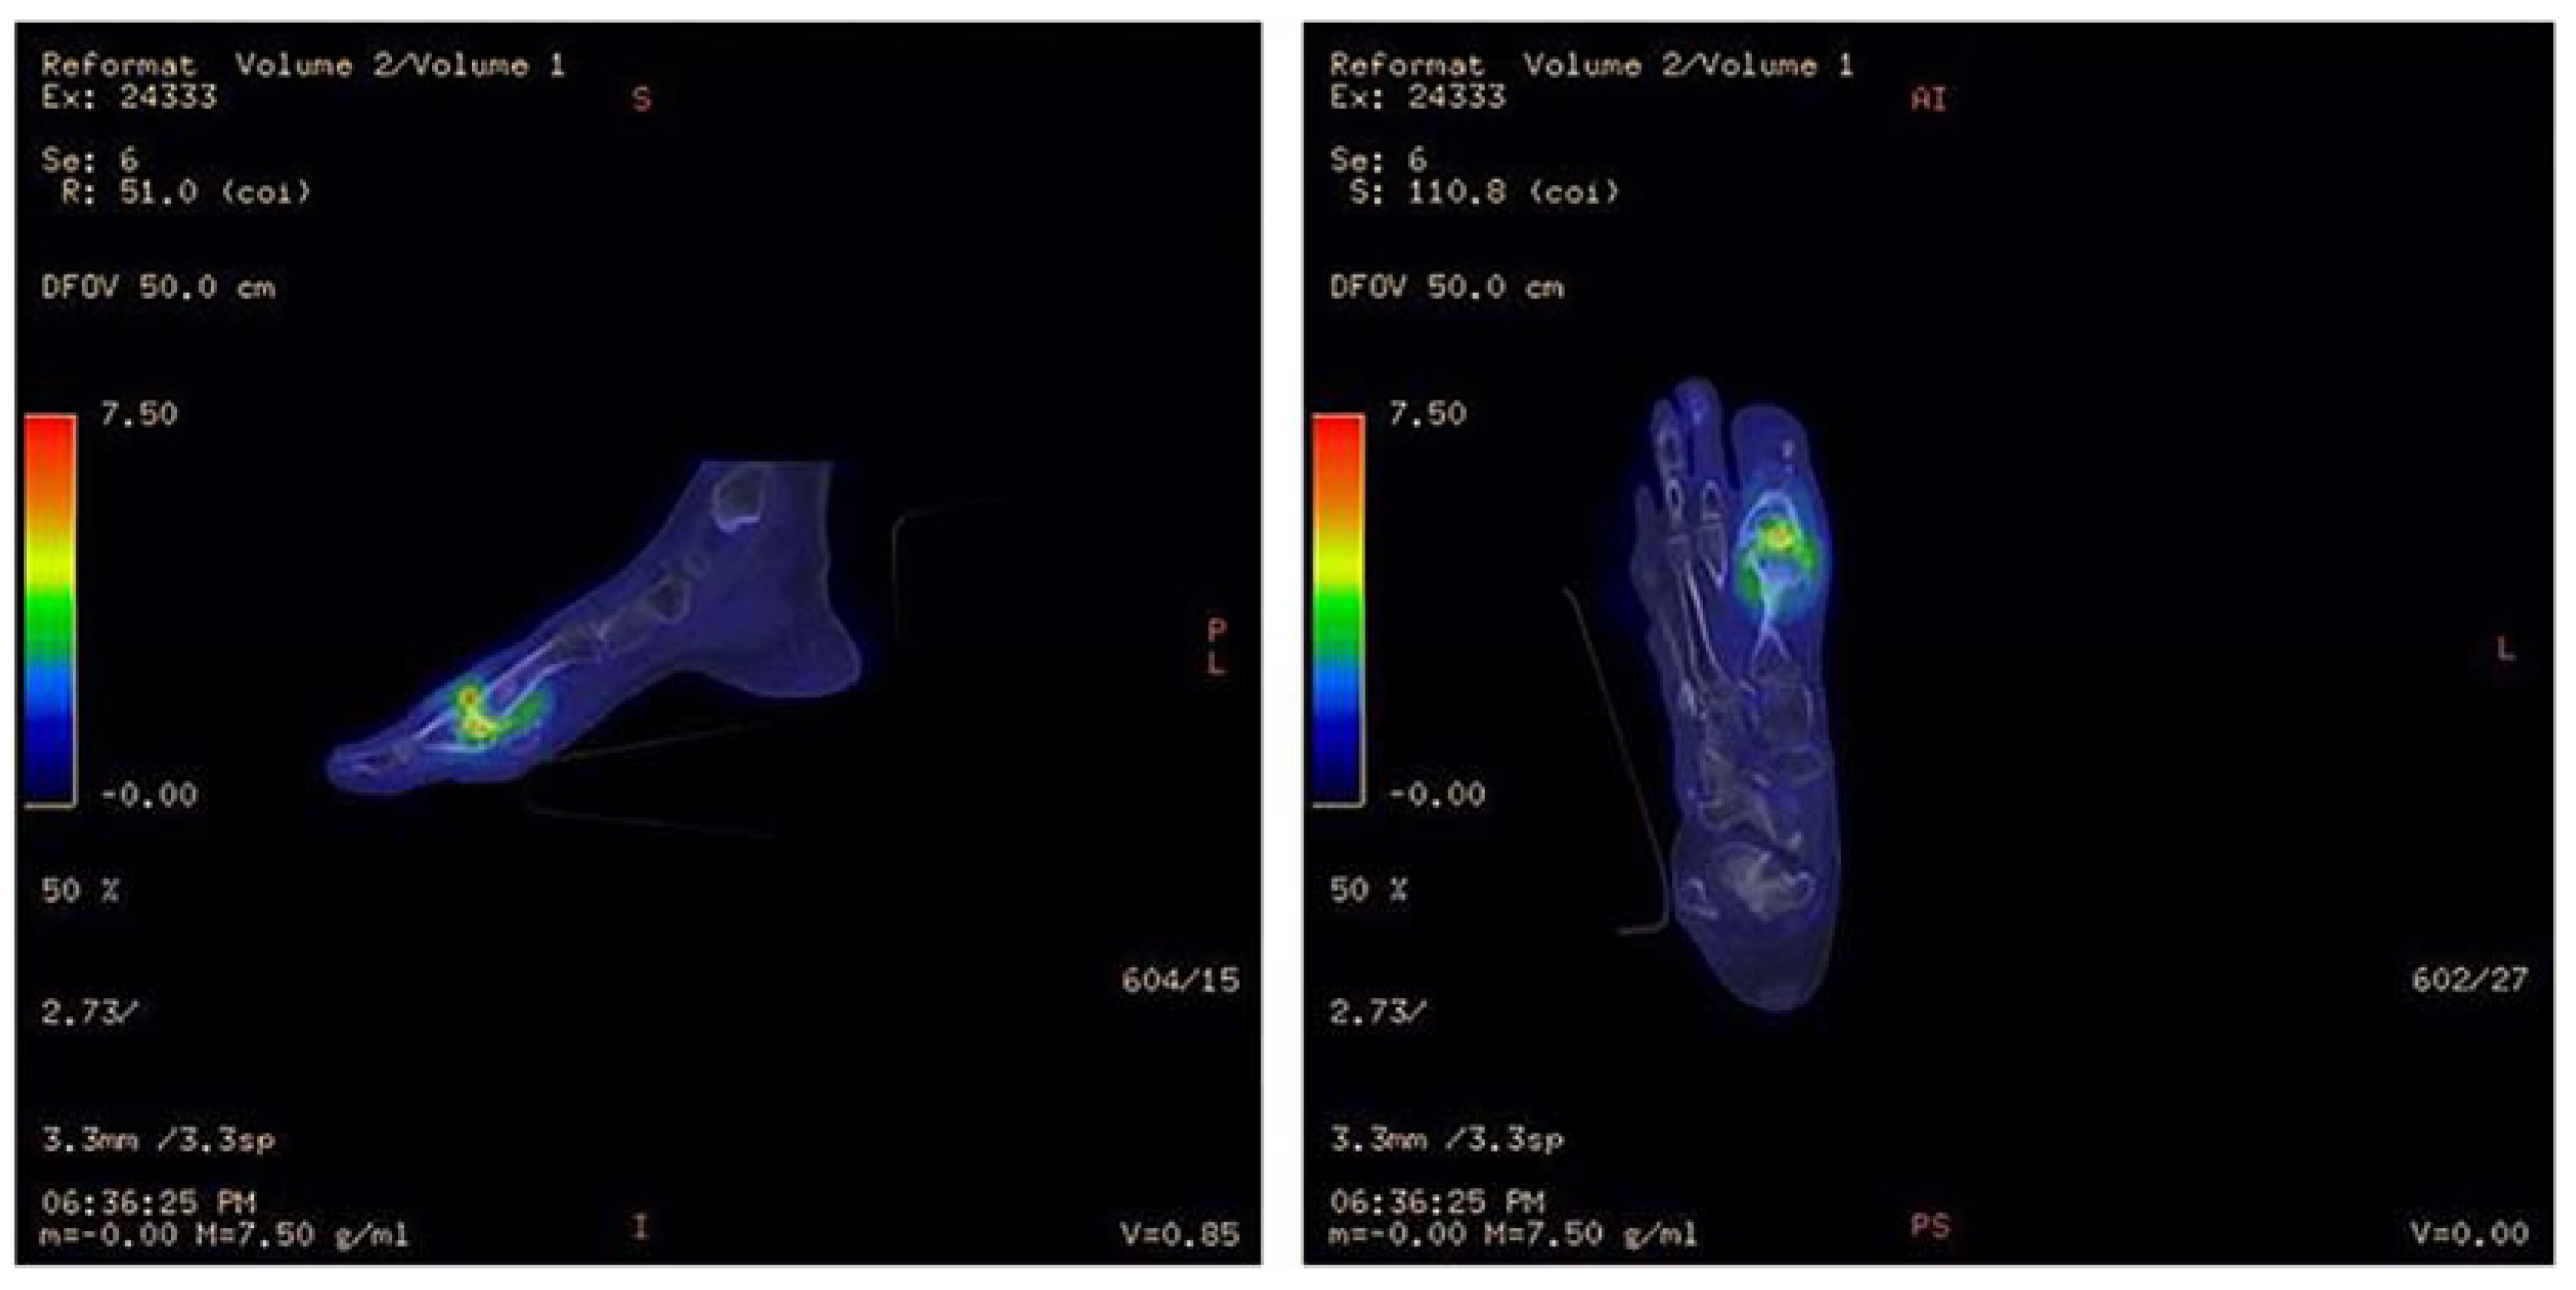

- Lazaga, F.; Van Asten, S.A.; Nichols, A.; Bhavan, K.; La Fontaine, J.; Oz, O.K.; Lavery, L.A. Hybrid imaging with 99mTc-WBC SPECT/CT to monitor the effect of therapy in diabetic foot osteomyelitis. Int. Wound J. 2016, 13, 1158–1160. [Google Scholar] [CrossRef]

- Erdman, W.A.; Buethe, J.; Bhore, R.; Ghayee, H.K.; Thompson, C.; Maewal, P.; Anderson, J.; Klemow, S.; Oz, O.K. Indexing severity of diabetic foot infection with 99mTc-WBC SPECT/CT hybrid imaging. Diabetes Care 2012, 35, 1826–1831. [Google Scholar] [CrossRef]